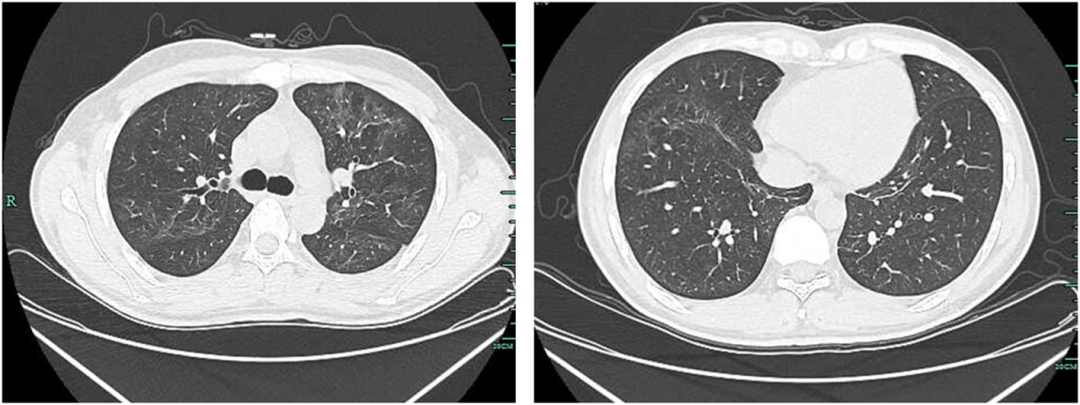

• 胸部CT显示左上肺有一个厚壁空洞,可见血管集束征和局部胸膜增厚(如图1所示)

图1:治疗前胸部CT显示左上肺厚壁空洞,内缘光滑,外缘不规则,邻近胸膜和左下胸膜增厚